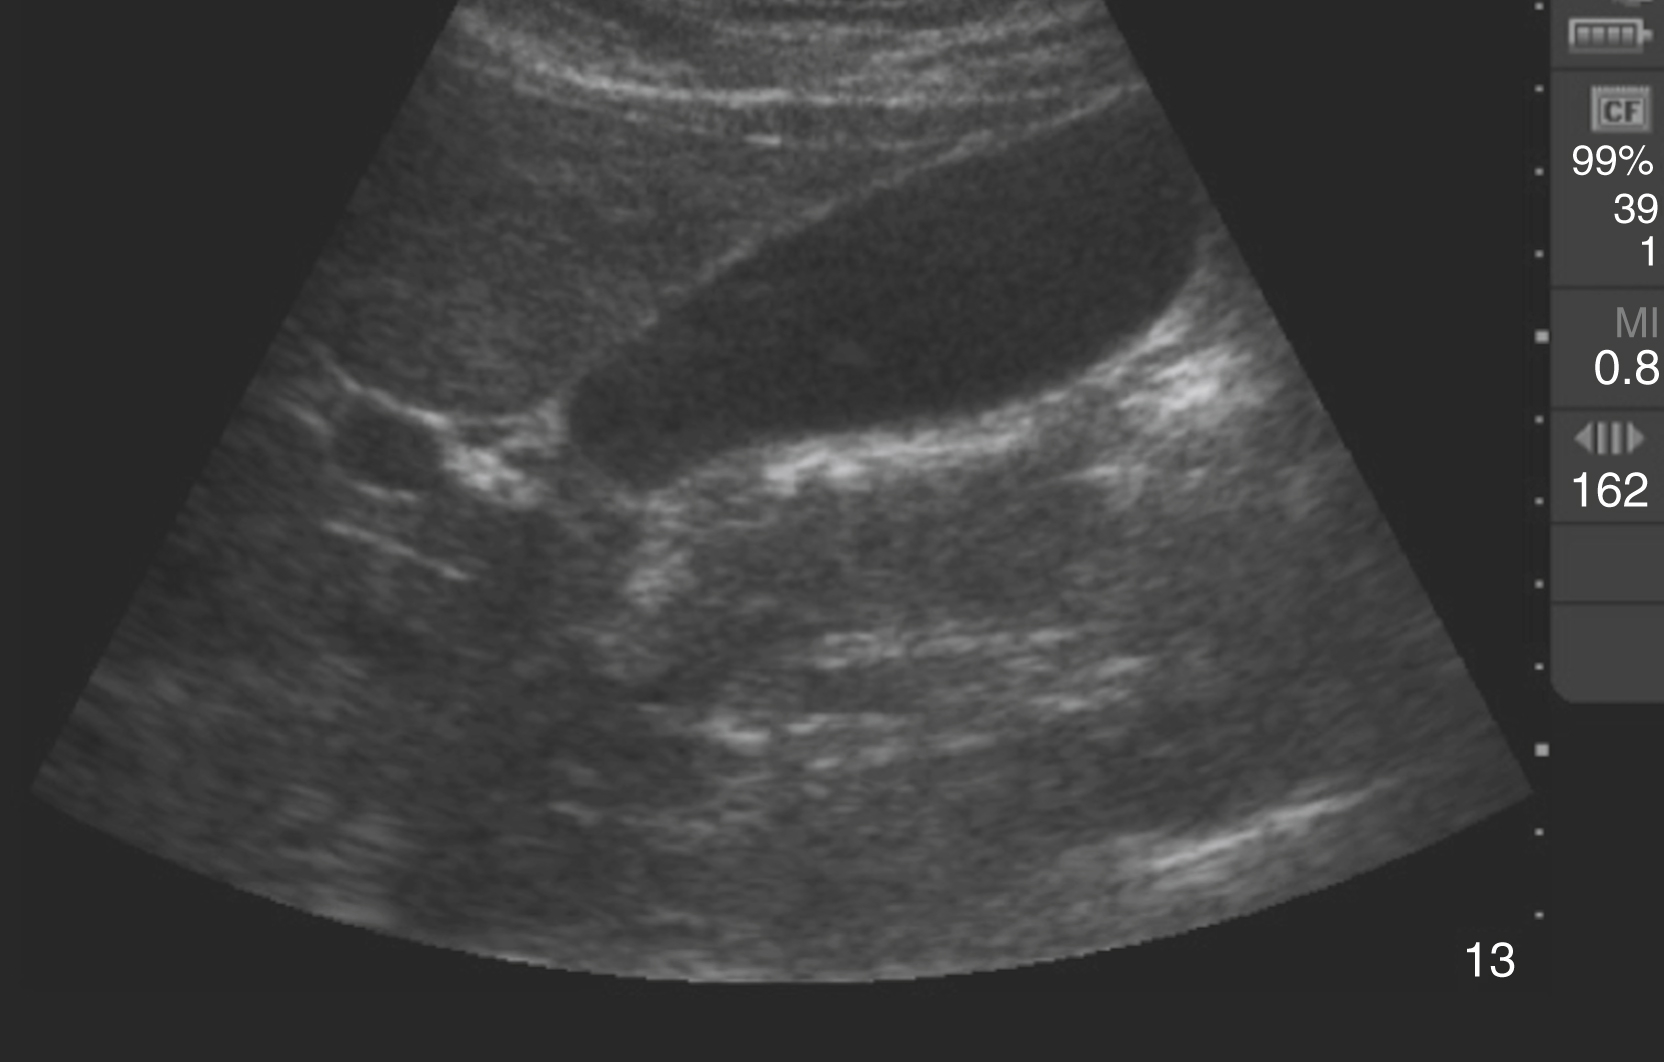

An aortic diameter greater than 3 cm constitutes an abdominal aortic aneurysm, but risk of rupture increases with size and is rare with aneurysms smaller than 4.5 cm ( Fig. e3.8 and Video e3.7 ). A linear echogenic flap, anywhere across the lumen of the aorta, is suggestive of aortic dissection and may be associated with a different Doppler flow pattern on either side of the flap ( Fig. e3.9 and Video e3.8 ). The cardiac US examination may demonstrate an unexplained pericardial effusion, a dilated aortic root (>4 cm), aortic insufficiency, and/or a linear echogenic flap in the descending aorta.

Transverse view of a AAA with mural thrombus.

Aortic dissection flap visualized on longitudinal view of the aorta.